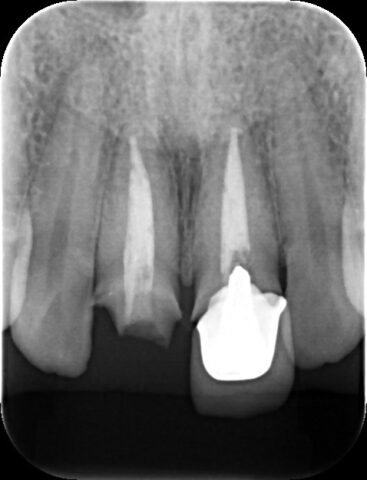

精密根管治療 治療前レントゲン

マイクロスコープを用いた、精密根管治療前後のレントゲンです。

精密根管治療 治療後レントゲン

治療後は根尖の病気はなくなり、骨が再生しています。

白くうつっている根管内の薬も緊密に充填することができているので、術後に細菌が侵入しづらく、病気の再発の可能性も低くなります。